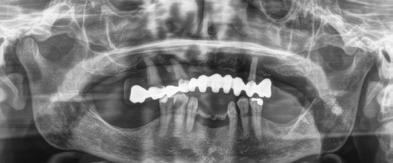

Estudios radiográficos finales

La radiografía lateral de cráneo en la Figura 11, se observa un ANB de 2° líneas rojas debido al avance del maxilar, una retroclinación del incisivo inferior a 76° líneas amarillas y mejoría de 1-maxilar a 122° líneas azules.

En la radiografía panorámica se ven 24 órganos dentales (Figura 12) después de realizada la cirugía osteotomía Lefort I maxilar de avance y una mentoplastía; las cuatro placas de fijación con sus respectivos microtornillos en el maxilar líneas de color rojo, la fijación con alambre quirúrgico de acero inoxidable señalados azules.

Figura 11. Radiografía lateral de cráneo. Figura 12. Radiografía panorámica.